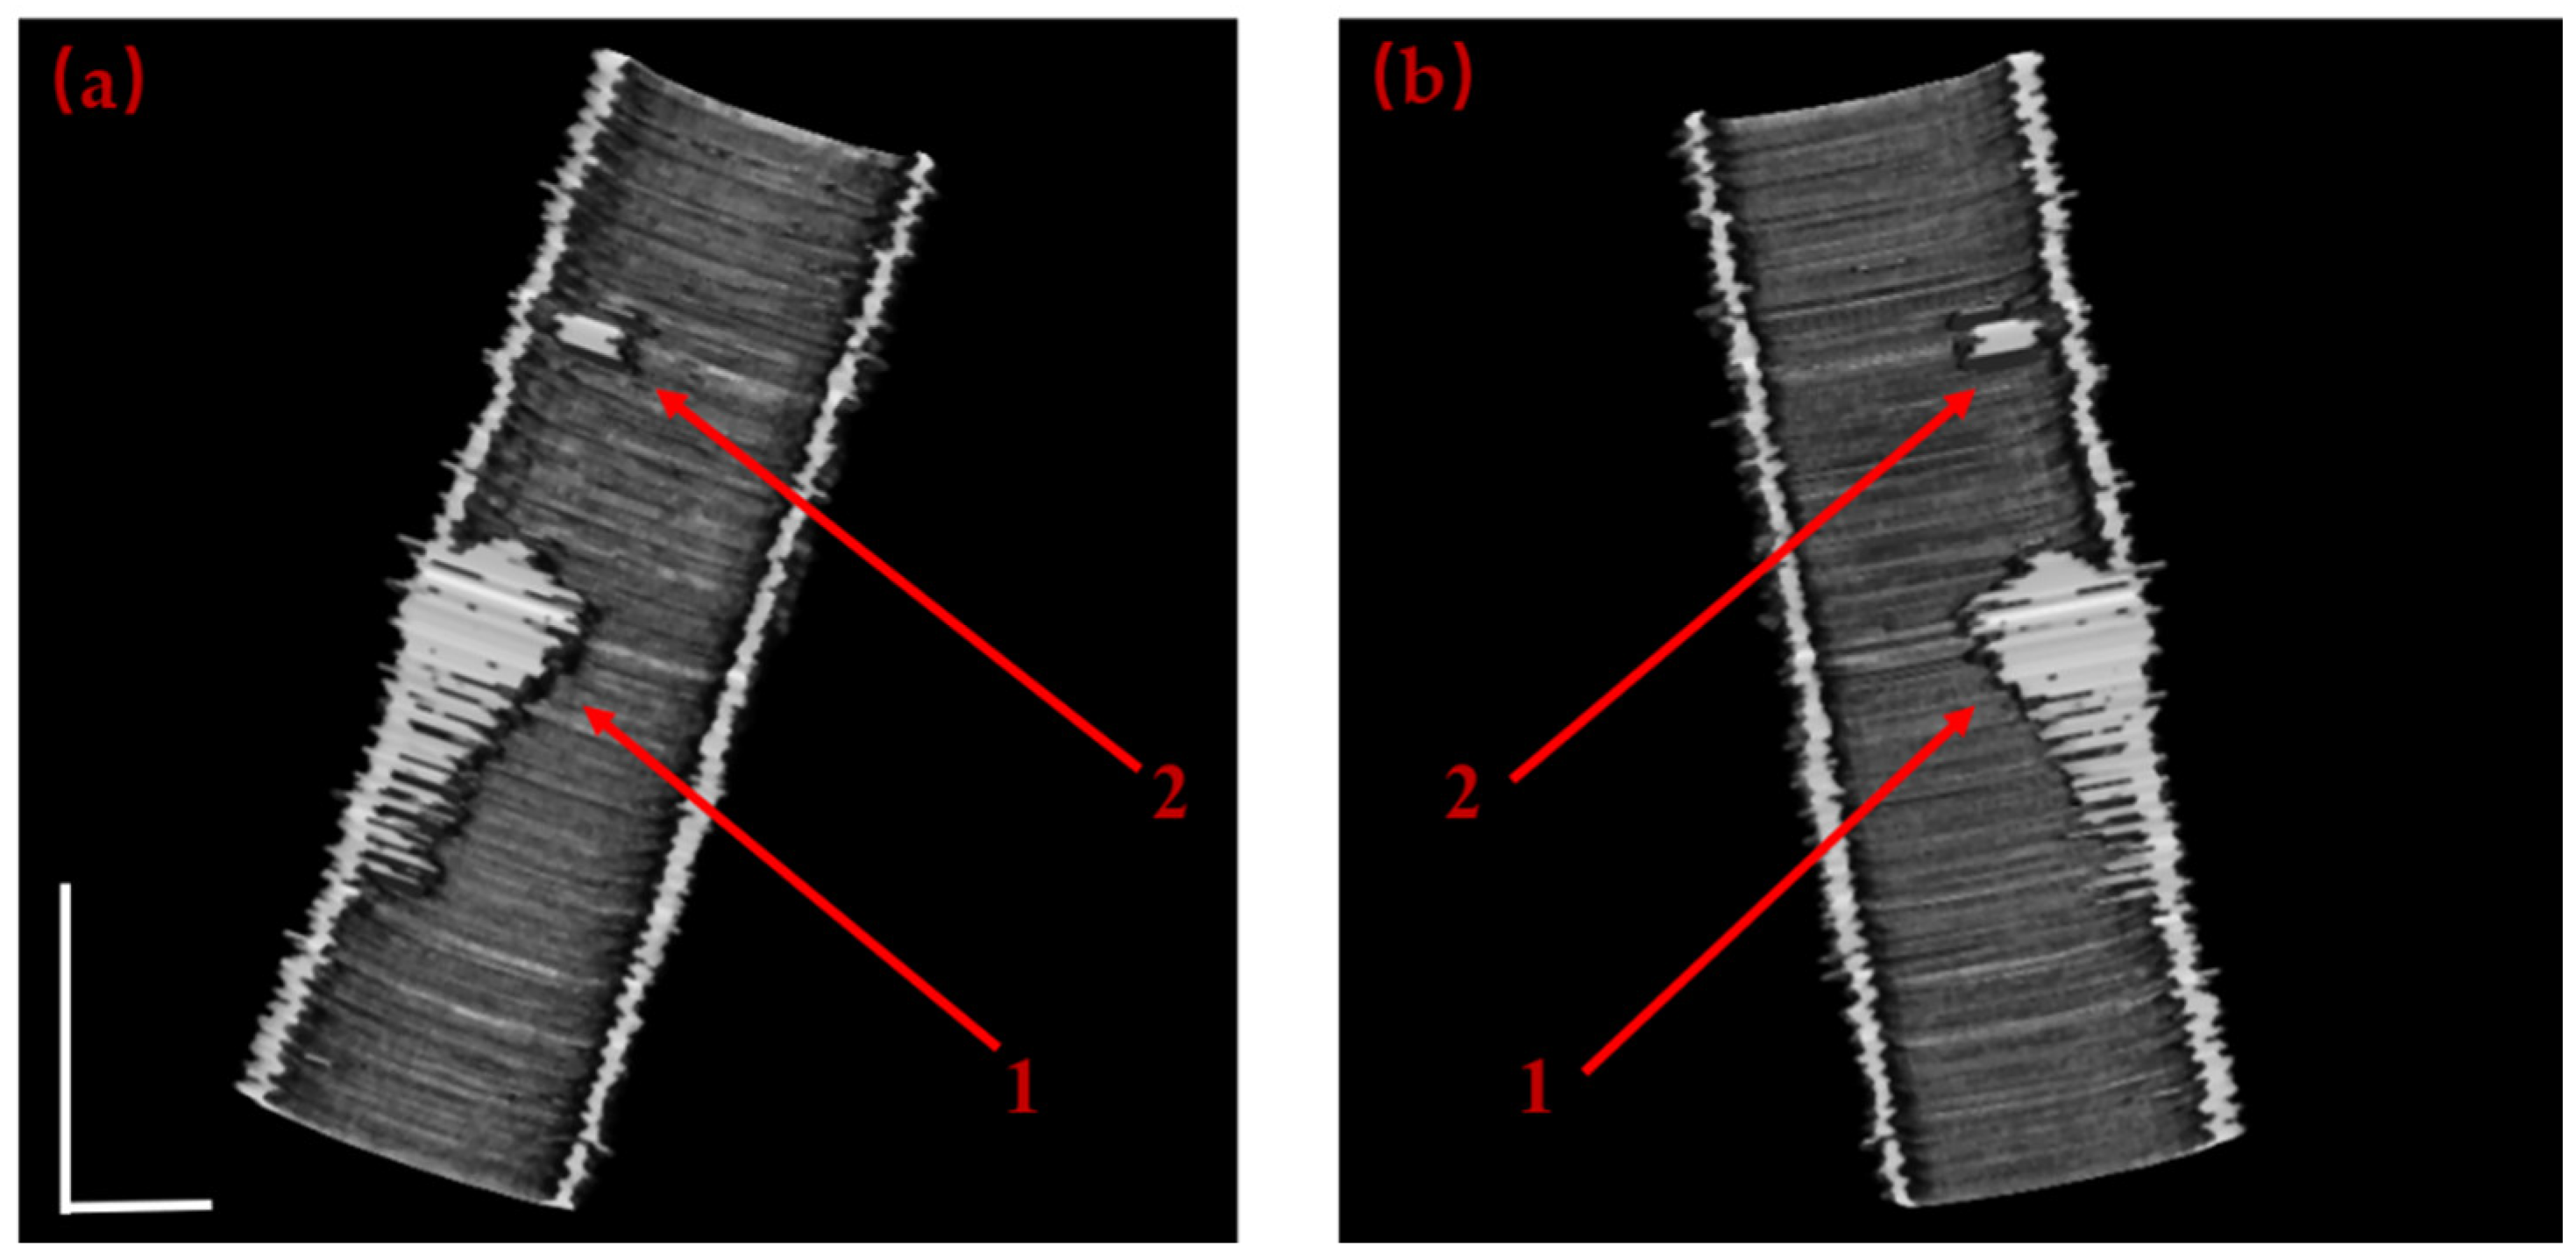

| Frame from Test Dataset | (a-1) | (b-1) | (c-1) | (d-1) |

| Precision | 0.977 | 0.964 | 0.971 | 0.947 |

| Recall | 0.985 | 0.979 | 0.982 | 0.962 |

| F1 | 0.963 | 0.958 | 0.965 | 0.953 |

| Dice | 0.968 | 0.965 | 0.976 | 0.954 |

| Frame from Test Dataset | (e-1) | (f-1) | (g-1) | (h-1) |

| Precision | 0.967 | 0.954 | 0.963 | 0.977 |

| Recall | 0.975 | 0.969 | 0.983 | 0.982 |

| F1 | 0.968 | 0.945 | 0.965 | 0.978 |

| Dice | 0.964 | 0.960 | 0.966 | 0.974 |